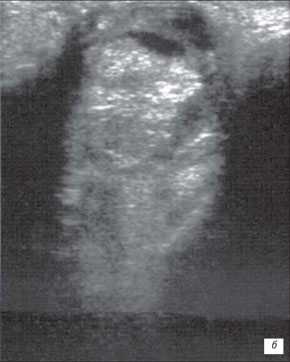

б) Большая ретинобластома. Опухоль заполняет практически всю заднюю камеру глаза. Структура опухоли неоднородна, средней эхогенности. Регистрируются множественные ярко белые (высокая эхогенность) отложения кальция..